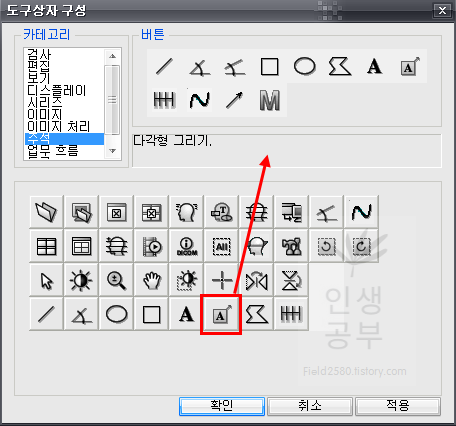

위와 같은 도구상자 구성 화면이 뜨게 됩니다. 아래에는 현재 사용중인 도구상자들이고 왼쪽 상단에는 도구상자에 넣을 수 있는 카테고리들이 있습니다. 카테고리칸 옆에는 버튼칸이 있고 아래 도구상자칸에 없는 메뉴들도 많이 있습니다. 아이콘에 마우스를 가져다 대면 간단한 설명이 나오니 필요하신 분들은 한번씩 다 확인해보시는 걸 추천해드립니다.

저 같은 경우는 선을 그리는 버튼도 많이 사용하니 추가해 줍니다.

카테고리에서 주석 메뉴를 클릭하면 오른쪽 버튼칸에서 2번째줄 2번째에 있는 것이 선그리기입니다. 위와 같은 방법으로 아래 도구상자란에 마우스로 끌어서 추가해줍니다.

그 다음으로 많이 사용하는 화살표 버튼을 추가해줍니다. 환자에게 설명할 때 포인트를 줄 때 많이 사용하니 추가해주시는 걸 추천해드립니다.

카테코리에 있는 모든 버튼을 보시는 것을 추천합니다. 위에 설명해드린 것은 제가 환자들과 함께 X-ray보면서 많이 사하는 것들이니 사용자에 따라서 선호하는 것들이 다를 수 있으니 한번 모두 다 보시고 추가할 것들은 추가하고 제거할 것들은 제거해주시는 것이 좋습니다. 카테고리에 있는 메뉴를 누르면 해당 메뉴에 버튼이 나오게됩니다. 이 버튼에 마우스를 가져대면 아래에 짧은 설명이 나오니 참고해주시기바랍니다. 어짜피 시간이 지나면서 잘 안쓰는 것들은 삭제하게 되니 필요에 따라서 삭제할 수도 있고, 필요한 것들은 다시 추가할 수 있으니 너무 많이 고민하지 않으셔도 됩니다. 본인에 맞게 메뉴가 세팅이 되었으면 적용버튼을 눌러줍니다.

만약 기존 도구상자 메뉴에서 필요없는 것들이 있어서 삭제해주고 싶다면 아래 현재 도구상자 메뉴 구성 버튼에서 필요없는 버튼을 눌러서 위쪽 버튼 메뉴를 설명하는 칸에다가 끌어다가 주면 사라집니다.